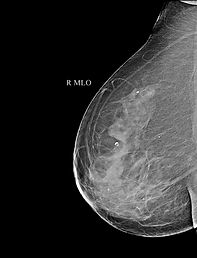

🔬 Superior Accuracy (FPD Technology): Equipped with an advanced Flat Panel Detector (FPD), our machine captures electronic images that can be magnified and manipulated on a screen. This allows our radiologists to detect the tiniest microcalcifications or masses years before they can be felt.

Older analog machines print images on physical film, which cannot be altered. A Digital Mammogram creates high-definition computer images. Our radiologists can zoom in, adjust the contrast, and examine dense breast tissue much more effectively, leading to vastly superior early detection rates.